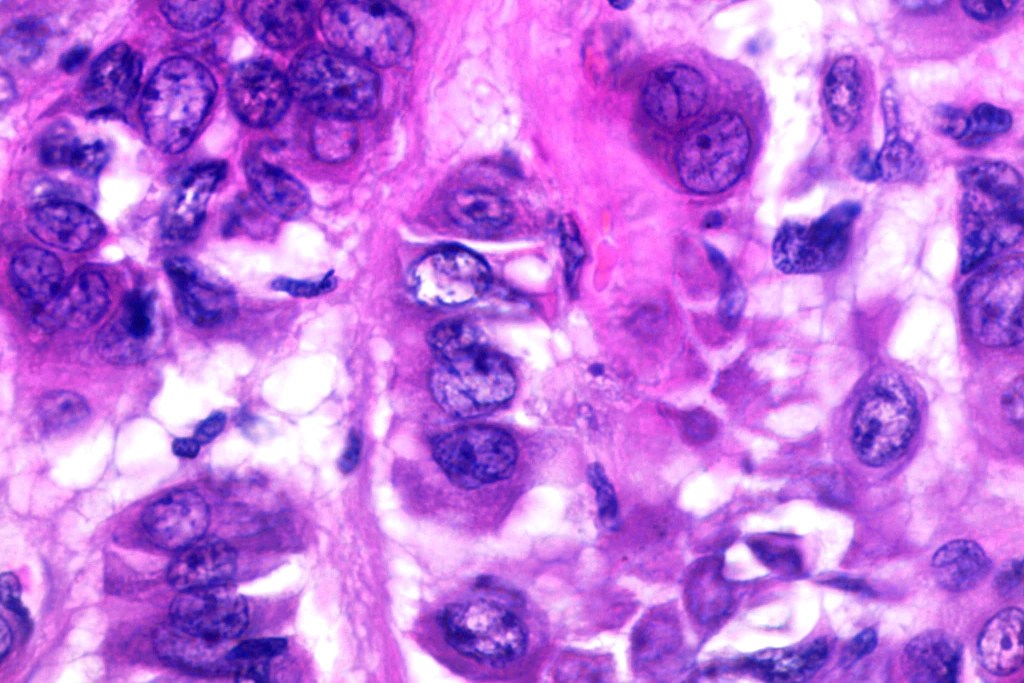

Histological features

•Well circumscribed unencapsulated, nodular/multinodular silhouette composed of an admixture of epithelial & mesenchymal elements

•Often intensely basophilic due to mucinous deposits

•Mixed epithelial component including nests & cords of epithelium with abundant, eosinophilic cytoplasm & small vesicular nuclei

•Clear cell change

•Glandular differentiation sometimes showing apocrine differentiation

•Myoepithelial layer in glandular foci

•Mucinous metaplasia

•Ductal differentiation

•Cribriform/retiform appearance occasionally evident

•Mitoses very rare or absent

•No necrosis

•Plasmacytoid myoepithelial cells; clear cell change

•Follicular & sebaceous differentiation

•Exceptionally matricial change

•Keratocysts & squamous foci

•Stromal sclerosis & hyalinization

•Myxoid change

•Chondroid foci

•Fat (lipomatous mixed tumor)

•Calcification & osteoid

•So-called eccrine variant characterized by a pure population of small ducts compressed by dense collagen

•So-called atypical variant characterized by severe atypia of the myoepithelial component (multinucleate & bizarre forms); benign behavior

•Epithelial cells are EMA, CEA & GCDFP-15 +ve, myoepithelial cells are S100, SOX10, SMA & MSA +ve